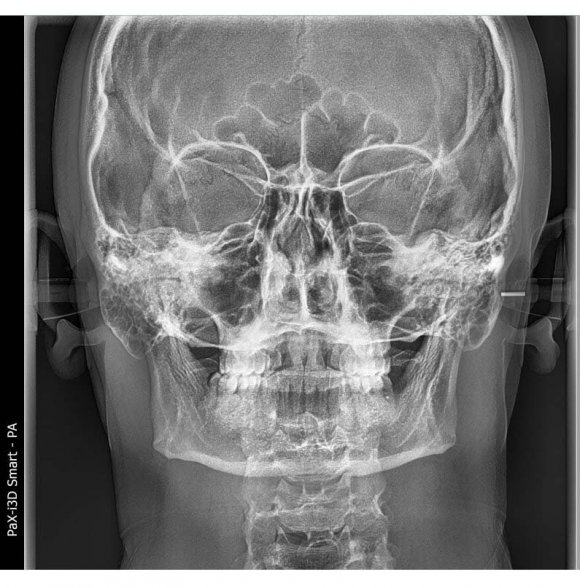

We described the comparison of the upper and lower jaws in such a perfect way that it is impossible not to use these indicators during this research. To determine the relationship of the upper and lower jaws to each other, a line is drawn from the Cg point to the J and Ag points on the right and left sides [9], the names of these points and lines are given in tables 1 and 2, and pictures 1 and 2. The right J and left J points are also connected, resulting in the formation of J-Cg-J triangle. Similarly, a horizontal line is drawn from the right Ag to the left Ag point and the triangle Ag-Cg-Ag is formed. These triangles are divided into two using MSR and four triangles: right J-Cg-MSR and left J-Cg-MSR; Ag-Cg-MSR and Ag-Cg-MSR are produced (Figure1). In this article, the authors compared the length of the sides of the triangles and evaluated their symmetry [6,9,10]. The indicators of the upper and lower jaw symmetry of representatives of the Uzbek population were determined, compared the indicators of men and women Grummons indicators (table 3). We compared the indicators of "comparison of the upper and lower jaws"of the representatives of the Uzbek population with normal physiologicalbite with the results of the average indicators of men and women. The J-MSR index for Uzbeks is 31.72±0.18 mm on the right and 31.69±0.17 mm on the left; in men, right 32.07±0.21mm. and left 31.96±0.21mm; right 31.25±0.25mm in women and left 31.33±0.27mm. equal to, and no significant difference was found when they were compared with each other or compared with the average values (P>0.05). Ag-MSR index in men is 42.6±0.25mm right and 42.49±0.29mm left; Ag-MSR index of women is 39.98±0.37mm right and 41.0±0.35mm left. is equal to It was found that the average of the Ag-MSR indicator of Uzbeks is equal to 41.49±0.25 mm on the right and 41.86±0.24 mm on the left. Now, when we compared Ag-MSR values of women and men with respect to mean Ag-MSR values, only female Ag-MSR R values were significantly different (P<0.05). When the Ag-MSR indicators of men and women were compared, it was found that there was a reliable difference between the Ag-MSR R indicator of men and the Ag-MSR R indicator of women (P<0.05). The average of the Cg-J indicator of Uzbeks is 68.82±0.47 mm on the right and 68.63±0.46 mm on the left. Cg-J index in men is 71.09±0.58mm right and 70.87±0.55mm left; in women, the right is 65.7±0.45mm and the left is 65.55±0.49mm. When comparing the Cg-J index of women and men, there are reliable differences in the Cg-J index of men compared to the Cg-J index of women (P<0.05). Now, when comparing the Cg-J index of women and men to the average of Uzbeks, a reliable difference was found only in men's Cg-J index compared to the average Cg-J index (P<0.05).

Figure 2: Comparison of upper and lower Jaws (Maxillo -Mandibular Comparison)